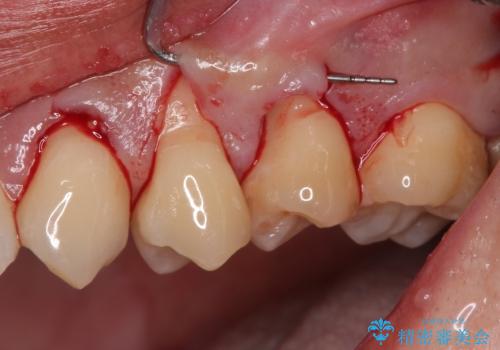

- 食いしばりと強いブラッシングにより、上顎小臼歯2本に知覚過敏を感じるようになったとのことで来院された患者様です。

歯肉退縮により歯根部が露出し、冷たい飲み物に痛みを感じる状態でした。

根面被覆を目的として歯肉移植術を行うこととしました。

歯肉が薄い状態であったため、歯肉退縮が起こりやすいと判断された患者様でした。

根面被覆を達成するとともに、歯肉の厚みを増すことで、今後歯肉退縮を起こしにくくするよう配慮した処置としました。